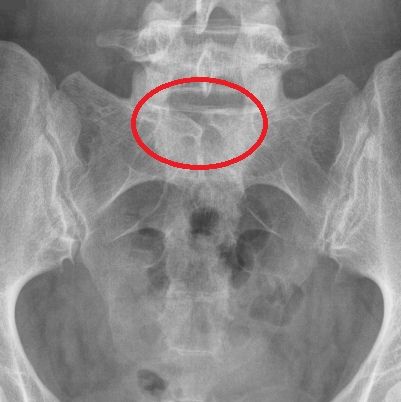

2) Инфантильная гемангиома ( рис 6С ) является сосудистым, как правило, приподнятым над уровнем кожи поражением, имеющим четко определенные границы. Ее легко отличить от плоских портвейновых, розовых или лососевых пятен, которые являются капиллярными пороками развития, и также описаны ниже, в разделе «Кожные аномалии среднего риска». Инфантильные гемангиомы развиваются у 5% младенцев и могут находиться в любом месте тела. Только инфантильные гемангиомы, которые располагаются на срединной линии тела над позвоночником, особенно в поясничной области, бывают связаны с лежащими под ними дистракными пороками развития.